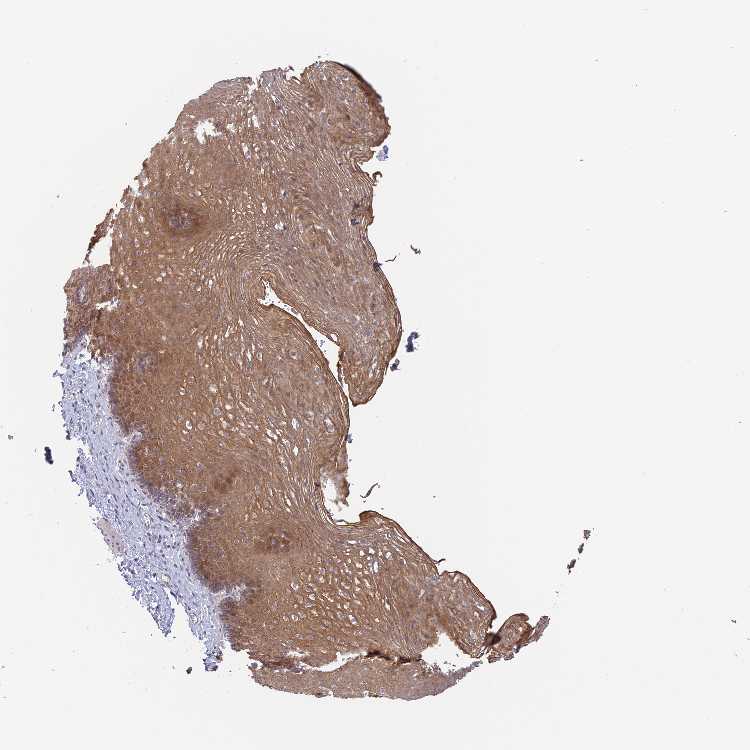

ESOPHAGUS - Antibody stainingi

Antibody staining in the annotated cell types in the current human tissue is reported as not detected, low, medium, or high, based on conventional immunohistochemistry profiling in selected tissues. This score is based on the combination of the staining intensity and fraction of stained cells.

Each image is clickable and will lead to virtual microscopy that enables deeper exploration of all samples and also displays staining intensity scores, fraction scores and subcellular localization as well as patient and tissue information for each sample.

Antibody HPA044686

Squamous epithelial cells Medium